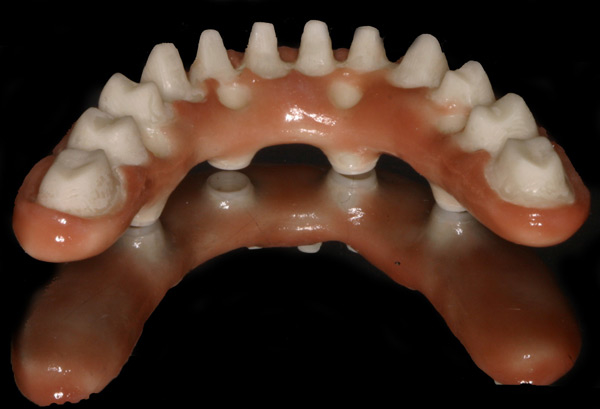

Problem: This patient had a series of problems that resulted with tooth loss. He also has a problem with sleep apnea. He wanted something fixed and stable.

Plan: Our plan… placed four implants on the lower with a fixed/hybrid prosthesis. Placed five on the upper arch with a titanium bar and snap attachments to allow a special one of the kind sleep apnea device.

He really likes his new smile and he gets a great nights rest as well.